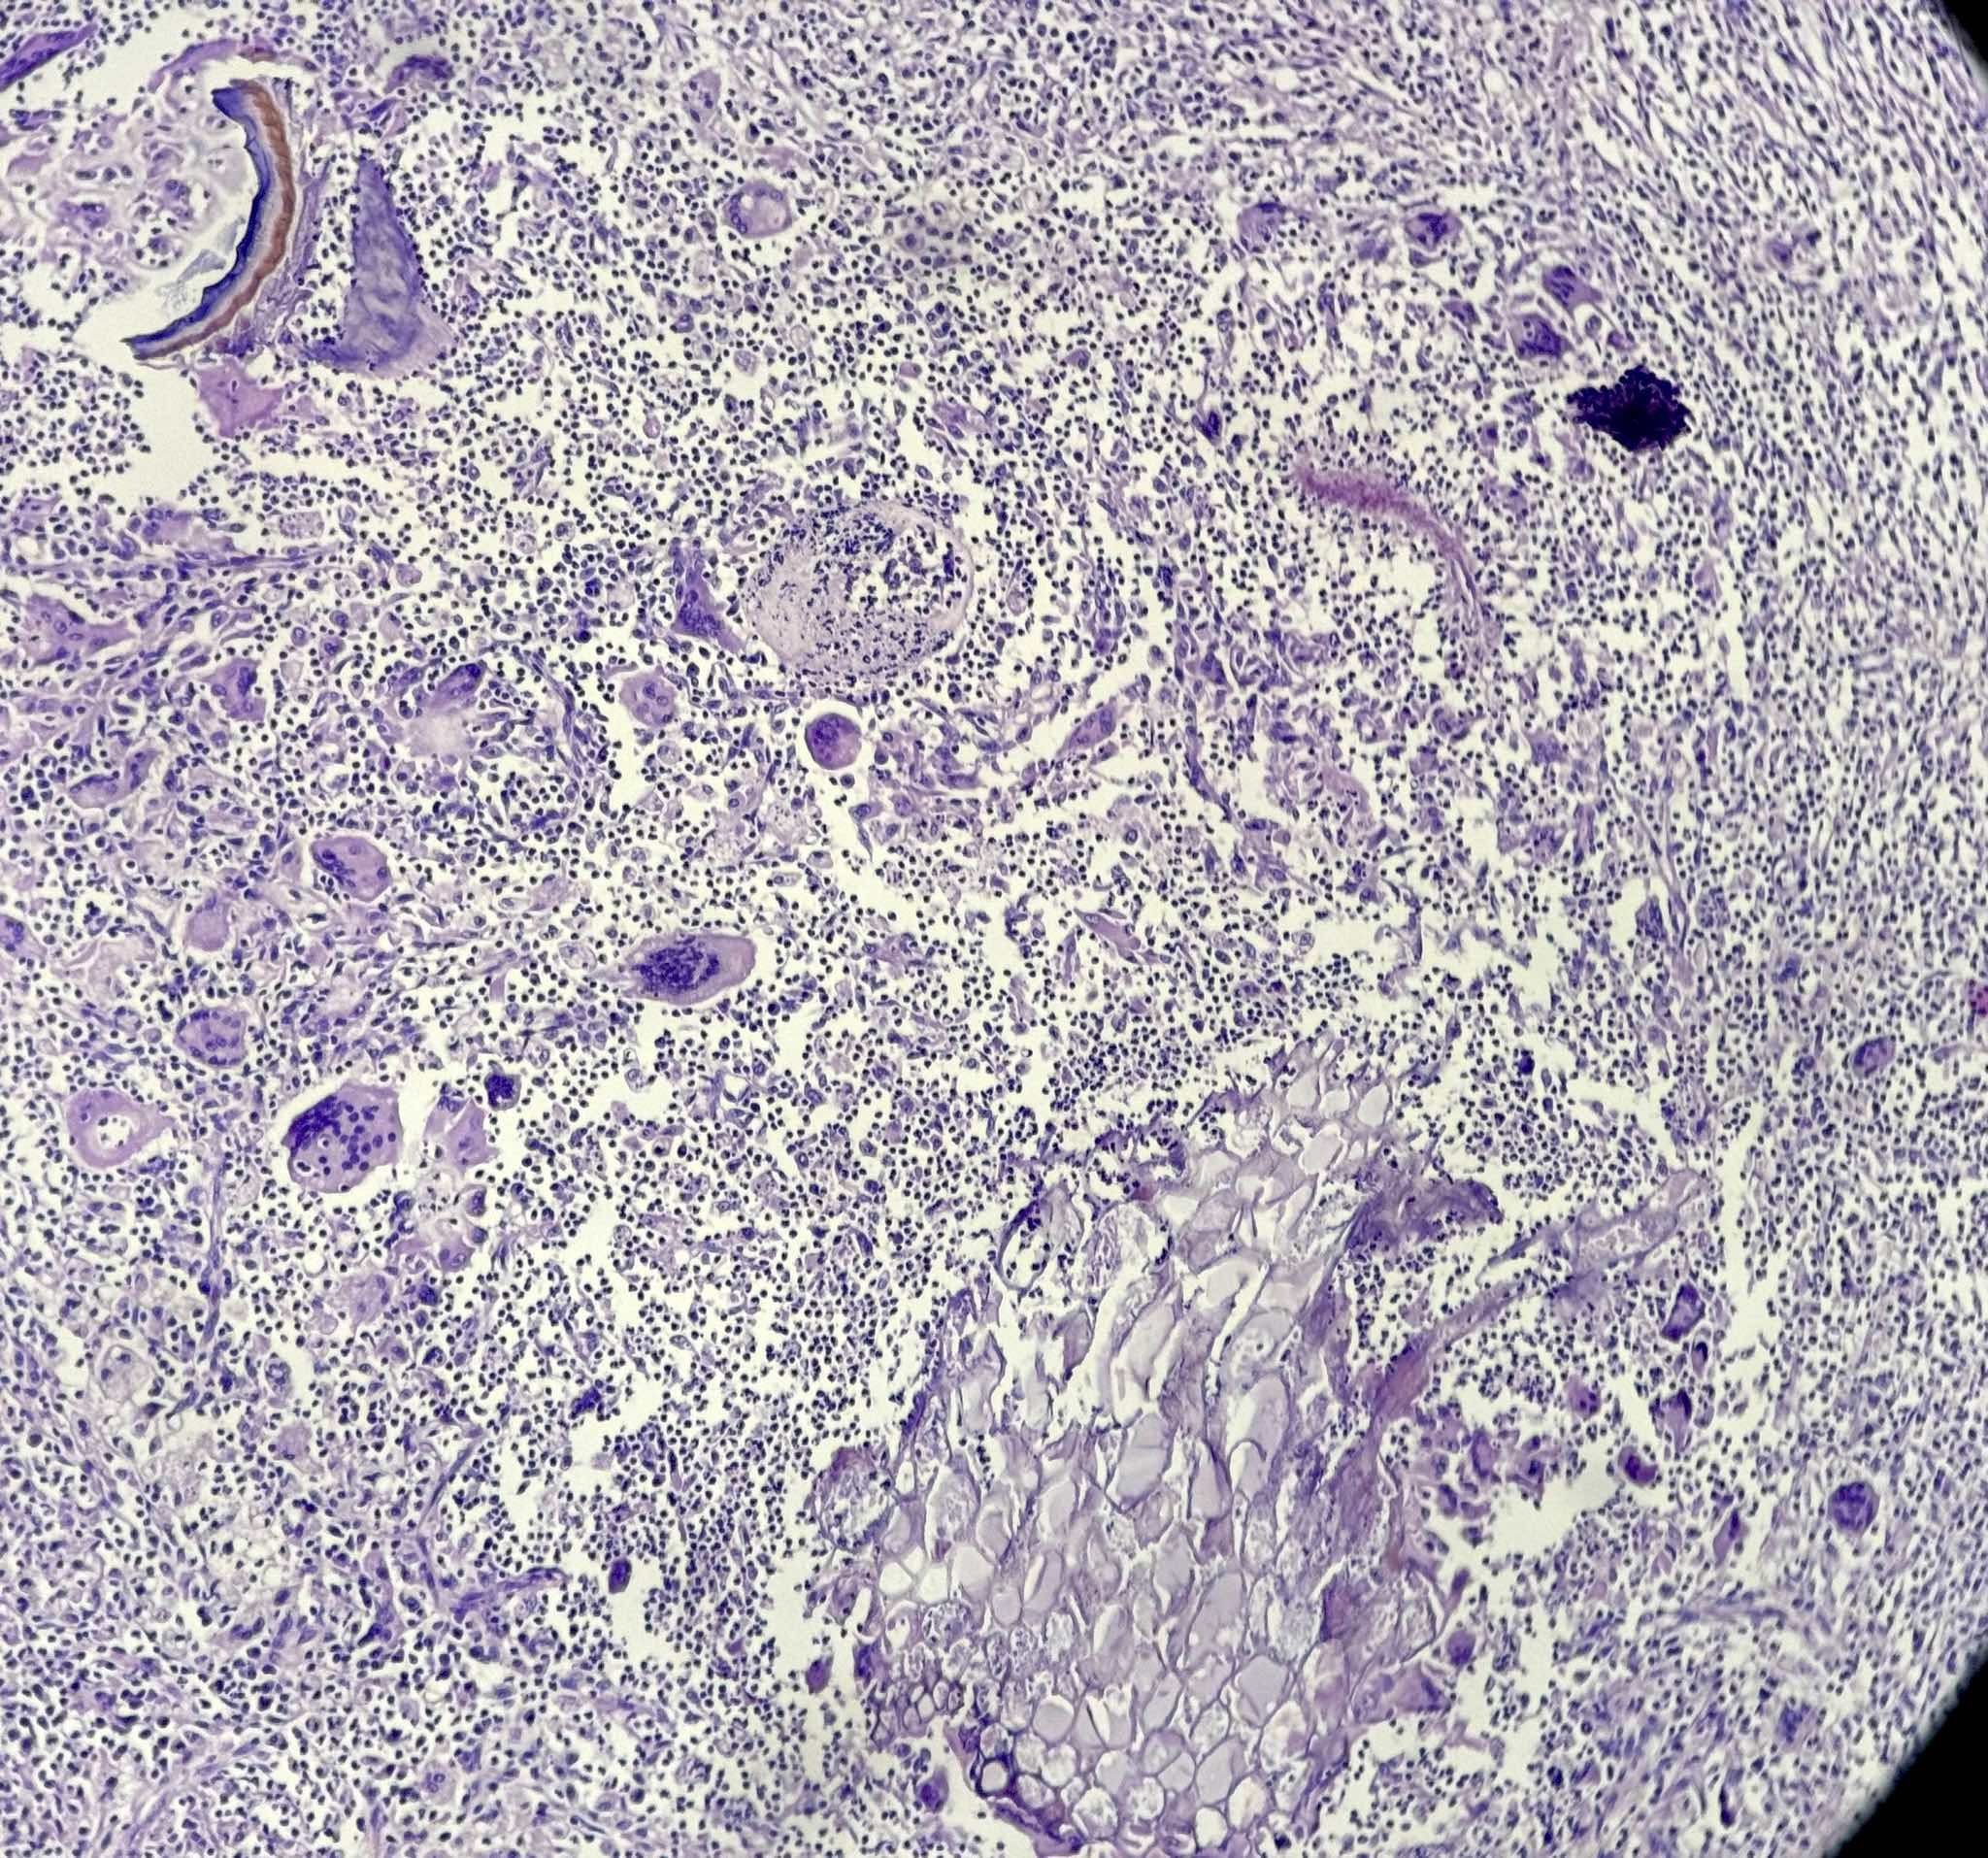

Microscopic (histologic) description

- Lobar pneumonia (Semin Diagn Pathol 2017;34:498):

- Uniform inflammatory infiltrate, the changes are at the same stage throughout the entire lobe

- Early stage: vascular engorgement, intra-alveolar fluid with few neutrophils and often bacterial colonies

- Massive confluent exudate with intra-alveolar neutrophils, red cells and fibrin, correlates with red hepatization on gross exam

- Progressive disintegration of red cells and the persistence of a fibrinosuppurative exudate, correlates with gray hepatization on gross exam

- Resolution phase: exudates converted to fibromyxoid masses rich in macrophages and fibroblasts

- Usually resolves with minimal fibrosis

- Pleuritis can be seen

- Bronchopneumonia:

- Most common pattern of pulmonary infection

- Different stages in the different areas

- Patchy intra-alveolar fibrinopurulent exudate with neutrophils

- Acute lung injury pattern:

- Diffuse alveolar damage (DAD): hyaline membrane formation

- Organizing pneumonia (OP): fibrohistiocytic proliferation with obliteration of small airways (fibroblast plug, Masson body), accompanied by inflamed surrounding alveolar interstitium

- Necrotizing pneumonia (Can Respir J 2014;21:239):

- Characterized by necrotizing inflammation, leading to alveolar septa disruption and cavity formation

- Common organisms: Staphylococcus aureus, Streptococcus pyogenes, S. pneumoniae (certain serotypes), Klebsiella, Acinetobacter, Pseudomonas and Burkhodoria

- Aspiration pneumonia:

- Foreign body giant cell reaction, characterized by multinucleated giant cells, granulomatous inflammation

- Often necrotizing, abscess formation is common

- Presence of food particles (e.g., lentils, vegetables, pill fragments)

Microscopic (histologic) images